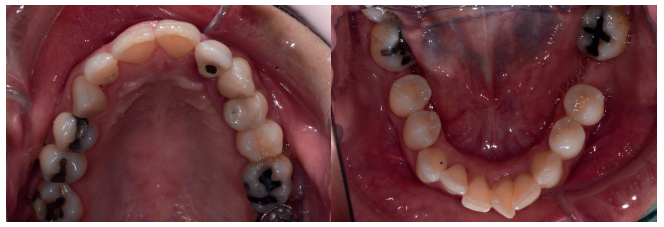

En la historia clínica, no se evidenciaron antecedentes médico-quirúrgicos de interés, alergias medicamentosas conocidas ni hábitos nocivos. A la exploración extraoral, se observó una línea de sonrisa media-baja (Figura 1). A la exploración intraoral, se apreciaron varias ausencias dentarias (1.7, 3.6 y 4.6) y un incisivo lateral superior izquierdo con una restauración fija dentosoportada (Figuras 2 y 3).